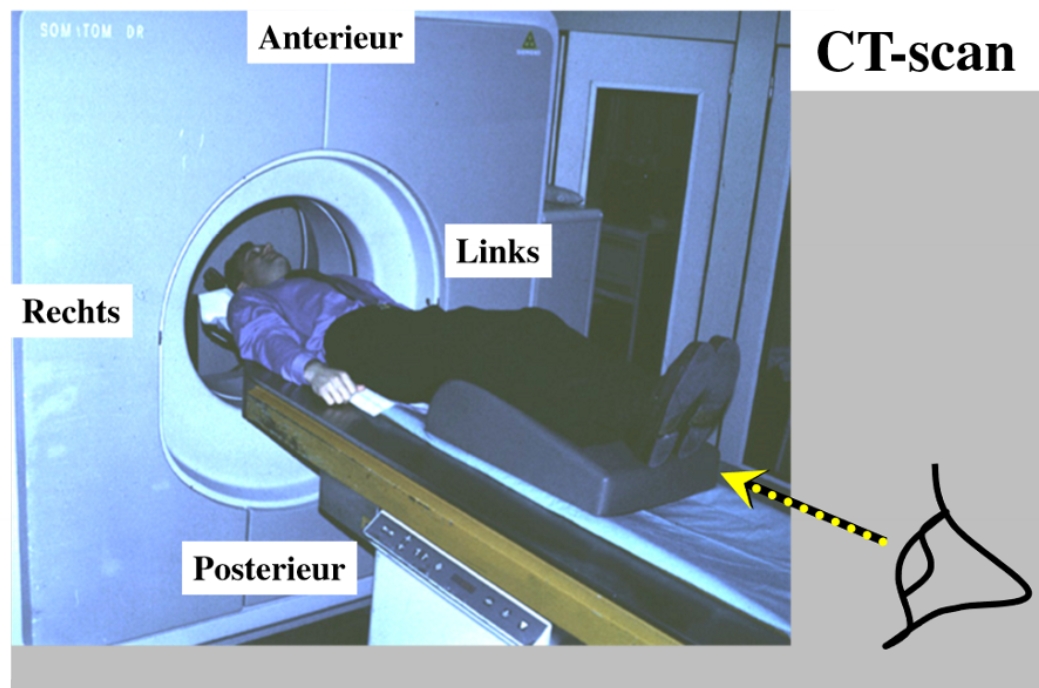

CT-scan

maakt dwarse doorsneden van de mens → salami